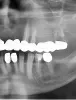

Женщине 72 года. У нее на этих зубах стоял мост из золота. Он начал качаться и немного спадать. На 7-ом зубе, мост двигался в горизонтальной плоскости влево вправо, а на 4-ом зубе сам этот зуб шатался с мостом в вертикальной плоскости (3-я степень расшатанности сказал на приеме ортопед, а потом терапевт, когда сняли мост). Как бы этот мост держался только на расшатанном 4-ом зубе.

Ортопед смотрел, когда мост еще стоял, сказал что 7-ой зуб под коронкой (мостом) сгнил и его надо удалять, и 4-й зуб тоже удалять. Мост снял ортопед по указанию терапевта-стоматолога. Ортопед рекомендовал эти два зуба к удалению вместе с мостом. Терапевт решил посмотреть на эти зубы без моста (коронки) и сделать выводы.

И так, мост сняли, и терапевт сказал, что 7-ой зуб удалять, а 4-й зуб, возможно, перестанет качаться через некоторое время после снятия этой нагрузки (моста), или его (4-й зуб) тоже удалить, потому что качается - 3-я степень расшатанности. В нашем случае я пытаюсь ухватиться за любую возможность сохранить эти зубы не удалять их.

Зубы стали подвижными из-за нарушения распределения жевательной нагрузки.

27-й зуб однозначно подлежит удалению ввиду атрофии костной ткани и кариеса корня. 24-й зуб можно попытаться сохранить, проведя ревизию канала и восстановив анатомию зуба. Дело в то, что 24-й зуб имеет один корень, 27-й трехкорневой зуб, а между ними отсутствует 25-й однокорневой и 26-й трехкорневой, то есть использовать 24-й зуб в качестве опоры нельзя, так как на него будет передаваться большая нагрузка, что приводит к атрофии костной ткани и, соответственно, подвижности зуба.